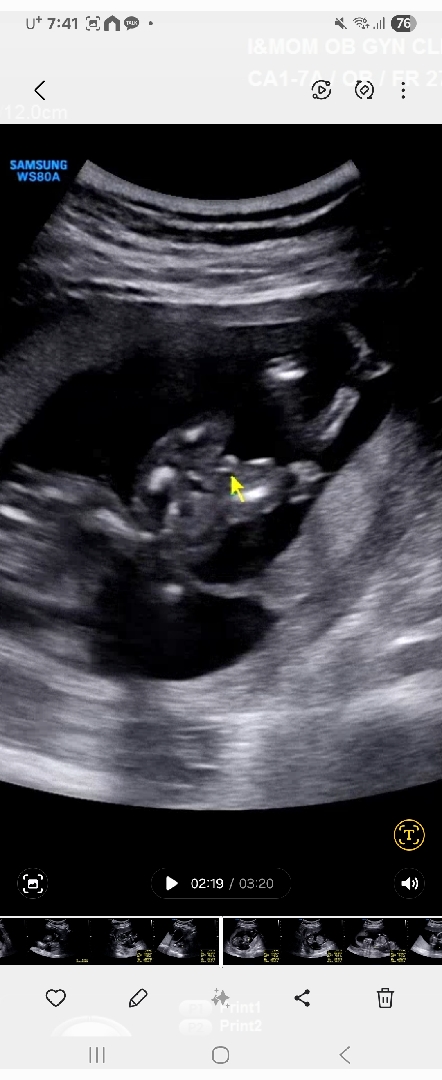

15주

이정도면 아들일가요